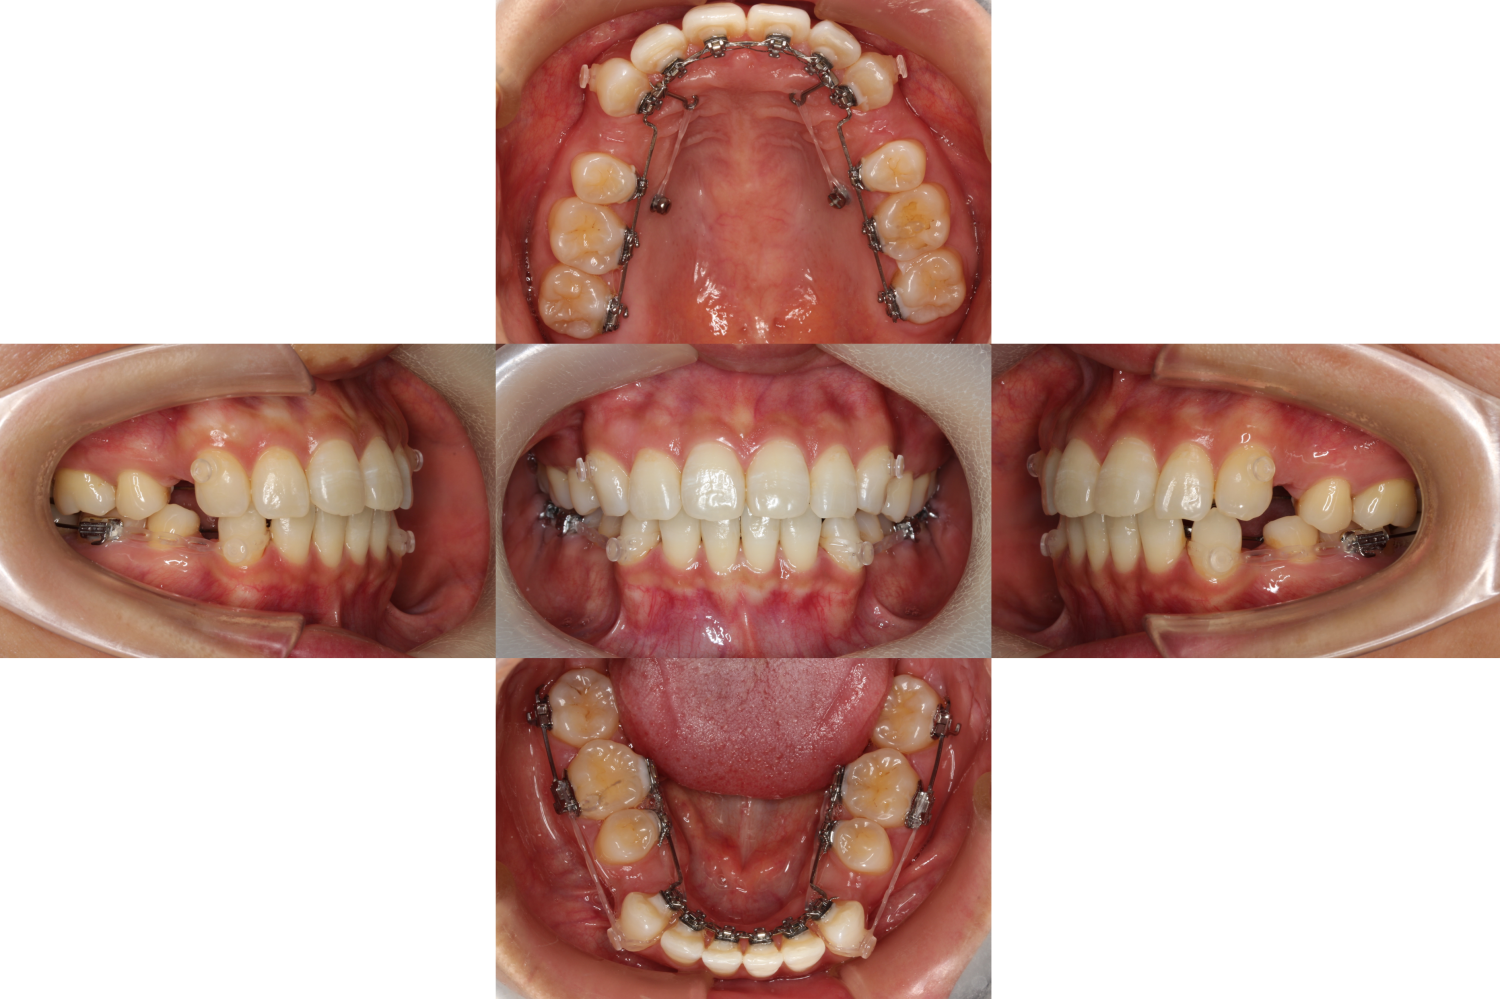

上下抜歯が終わり装置を装着しました。

抜歯した部分のワイヤーが舌に当たって痛むため、

透明のチューブを通し不快感を軽減しました。

上下の歯の凸凹が無くなり一直線に並びました。

前歯を下げるために、スクリューとゴムを使って後ろに引いていきます。